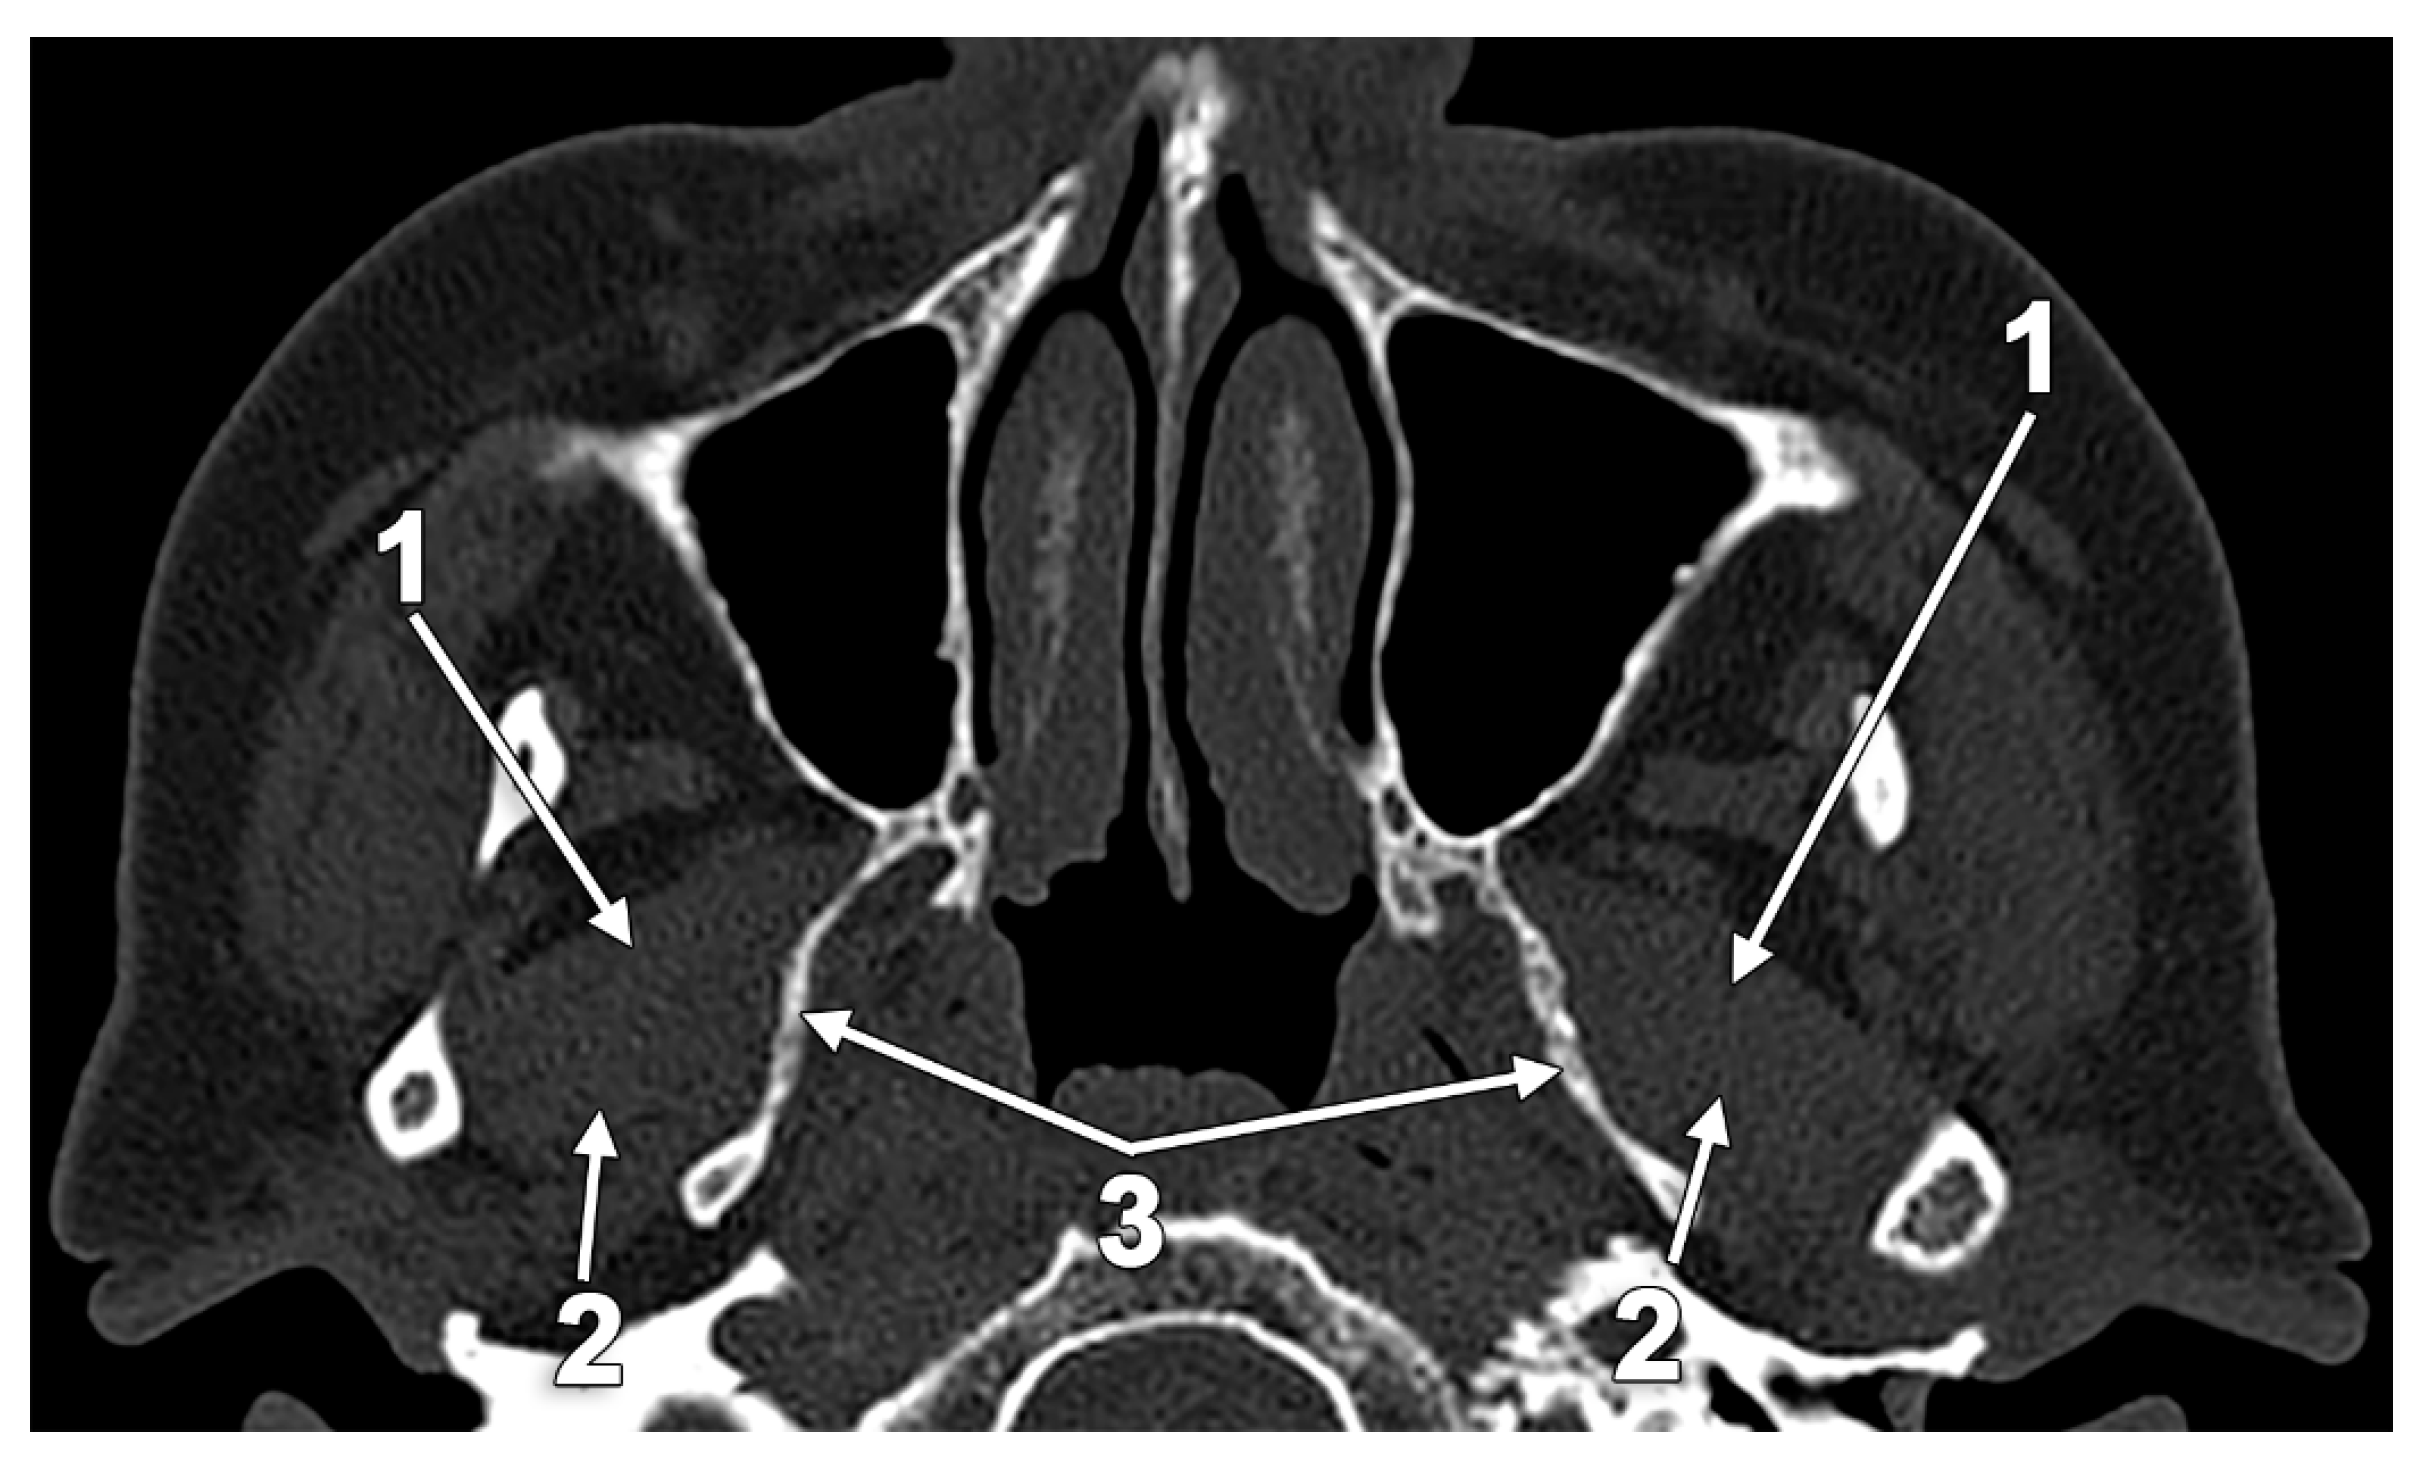

5.1. Broad Lateral Pterygoid Plates

5.2. The Pterygospinous and Pterygoalar Bars